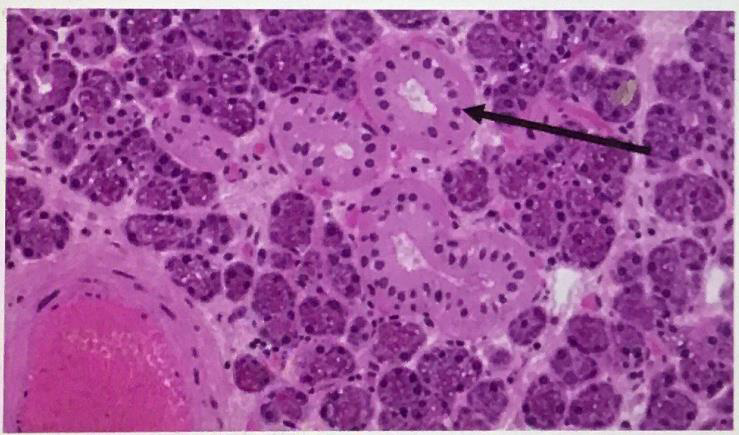

Circumvallate papillae

Foliate papillae

Fungiform papillae

taste bud

Von ebner’s gland

taste pore

Mucous gland

Serous gland